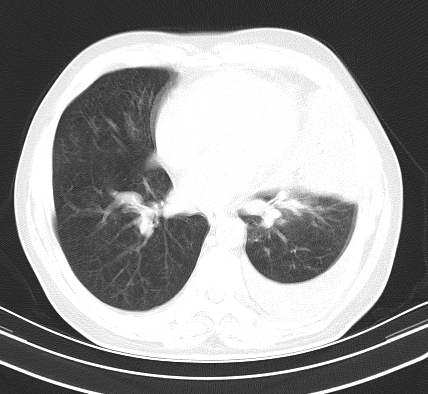

以下是引用老爱克斯新网客在2008-7-31 6:30:00的发言:[br]左肺上叶大片状病灶,左肺上叶支气管狭窄呈鼠尾状,左肺门增大,纵隔内见肿大淋巴结,左侧胸腔积液,余肺清晰。左肺中心型肺癌淋巴结转移,

以下是引用zjb在2008-7-31 6:32:00的发言:[br]左侧中心性肺癌 阻塞性肺炎 肺不张 胸腔积液 建议气管镜

以下是引用zjzjr在2008-7-31 8:45:00的发言:[br]考虑左侧中心性肺癌伴阻塞性肺炎,左肺上叶肺不张,纵隔淋巴结转移;左侧胸腔积液。建议行纤支镜检查。

以下是引用sdzyy在2008-7-31 8:47:00的发言:[br]病灶较治疗前有所进展,胸水增多, 左侧中心性肺癌 并 阻塞性肺炎 肺不张 胸腔积液 可能性大; 建议气管镜检查。 [br] [br]